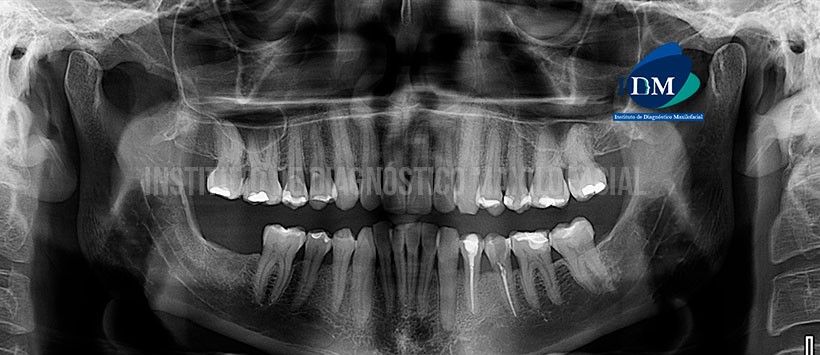

Paciente de 48 años de sexo masculino, acude al Instituto de Diagnóstico Maxilofacial para evaluación de la pieza 35 con antecedente de tratamiento de conducto por traumatismo dentario.

A la evaluación de la radiografía panorámica se evidencia que la pieza 35 tiene material d obturación de conductos perdida de estructura dentaria por mesial. (Figura 1)